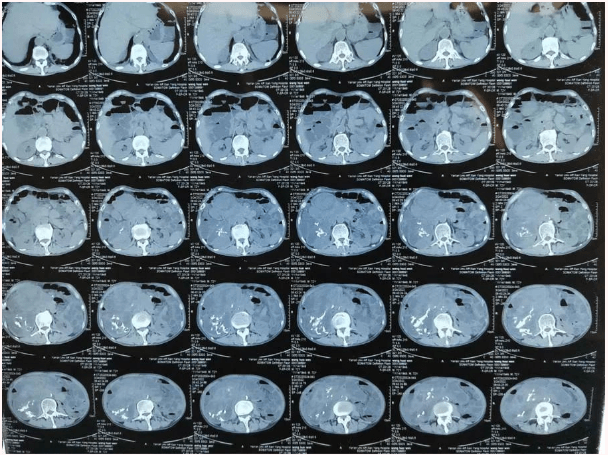

患者王大爺,男,72歲,發(fā)現(xiàn)腹腔腫物10余年,近兩年來患者雙下肢乏力、貧血,依靠間斷輸血維持著正常生活,出現(xiàn)頭昏,行動(dòng)困難,腹部疼痛及便血慕名來我院就診。入院后查體評(píng)估患者年齡大,體質(zhì)差,嚴(yán)重貧血,肺部感染及腸梗阻征象,腹部增強(qiáng)CT檢查提示腹膜后巨大腫瘤,長徑超過30厘米,占據(jù)大部分腹腔,并可能存在雙原發(fā)腫瘤。

苗滿園腫瘤外科團(tuán)隊(duì)在麻醉科/手術(shù)室的緊密配合下為該患者進(jìn)行手術(shù),術(shù)中發(fā)現(xiàn)腫瘤巨大,幾乎占據(jù)了整個(gè)腹腔,從左側(cè)向右腹腔延伸,向上將肝、腎擠向膈下,向左將胃及小腸擠向左上腹,向下深達(dá)盆腔內(nèi),包繞下腔靜脈、腸系膜上動(dòng)脈等大血管及輸尿管,回盲部及回腸也受侵犯。手術(shù)難度巨大,風(fēng)險(xiǎn)極高。團(tuán)隊(duì)?wèi){借著高超的手術(shù)技能和精準(zhǔn)的手術(shù)預(yù)案沉著應(yīng)對(duì),迎難而上,應(yīng)用高頻電刀、超聲刀、切割縫合器等先進(jìn)設(shè)備,耗時(shí)近5小時(shí)為患者切除了巨大腹腔腫瘤,并聯(lián)合右半結(jié)腸切除,術(shù)中出血僅50ml。術(shù)后病理為腹膜后巨大平滑肌瘤+回腸腺癌。